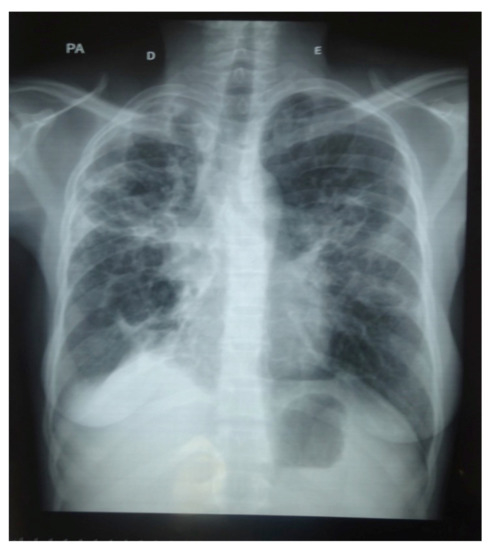

3. Results